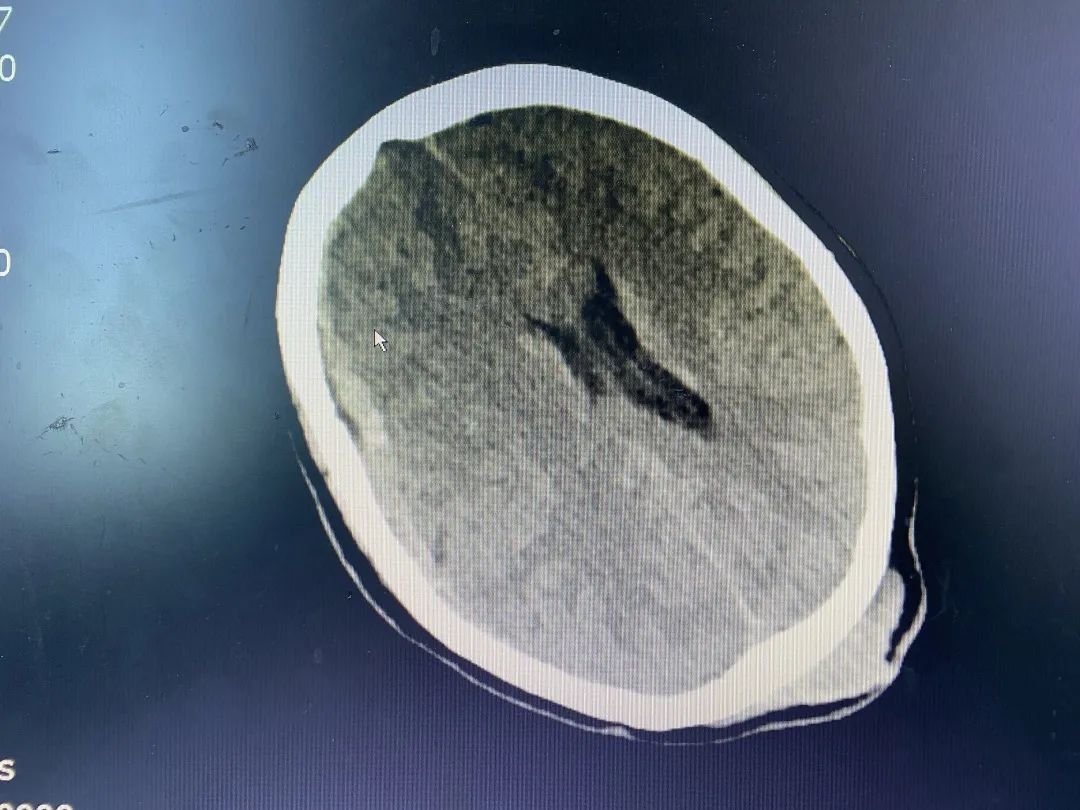

4月下旬的一天中午,急診科門口傳來一陣急促的救護(hù)車鳴笛聲,車上推下來了遭遇嚴(yán)重顱腦外傷的沈阿婆。急診科值班醫(yī)生迅速檢查患者病情并給予相關(guān)輔助檢查,顱腦CT提示:枕骨骨折,伴枕頂部皮下血腫;考慮右側(cè)額顳頂部硬膜下血腫;蛛網(wǎng)膜下腔出血;右側(cè)額葉高密度灶,腦挫裂傷可能;雙側(cè)基底節(jié)區(qū)腔隙灶,腦萎縮。

▲患者術(shù)前CT

神經(jīng)外科值班醫(yī)師會(huì)診后發(fā)現(xiàn)患者出血量大、腦疝形成、神志呈昏迷狀態(tài),病情十分危重,亟需手術(shù)治療。我院神經(jīng)外科立即給予減輕腦水腫,并與福醫(yī)大附二院神經(jīng)外科當(dāng)值專家取得聯(lián)系,共同研討患者病情。征得家屬同意后,在福醫(yī)大附二院當(dāng)值專家趕往我院的同時(shí),神經(jīng)外科積極做好術(shù)前準(zhǔn)備,專家到位后第一時(shí)間將患者送入手術(shù)室予急診全麻下行“右額葉腦內(nèi)血腫清除術(shù)+右額顳頂硬腦膜下血腫清除術(shù)+顱骨去骨瓣減壓術(shù)”,術(shù)后安返ICU進(jìn)一步治療,復(fù)查CT,血腫大部分清除。